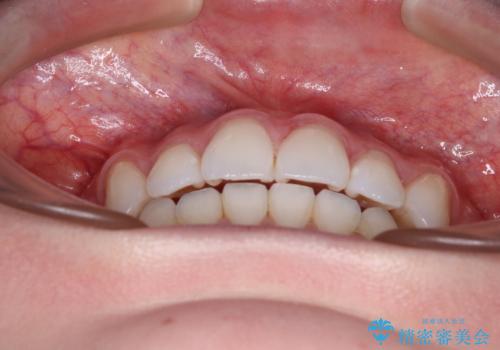

- 左右の八重歯を気にして来院された患者様です。

歯列としてはインビザラインでもワイヤー矯正でも対応できるものでしたが、インビザラインによる治療を希望されていました。

上顎の八重歯改善にインビザラインでは時間のかかってしまう可能性があり、更には口元が治療前よりも突出してしまう可能性があったため、補助装置により八重歯を事前に引き込んでおくことで、インビザラインによる治療をスムーズに行えるように計画しました。

補助装置を使用したことで、口元が突出することもなく、スムーズに仕上げることができました。